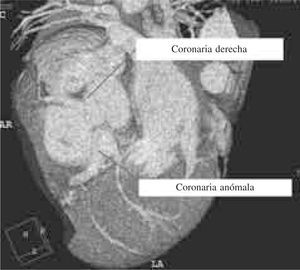

Una adecuada y precisa identificación anatómica de una malformación de estas características es parte fundamental para su estudio y la corrección definitiva, por lo que se practicó angiotomografía coronaria, en la que se observó con mayor claridad el origen real del tronco anómalo (Fig. 3). Ello orientó para tomar una decisión acerca del plan quirúrgico inicial, ya que lo consideramos distante para realizar una corrección anatómica con reimplante del botón coronario o una tunelización, procedimientos de primera elección en esta enfermedad, dejando como posibilidad inicial la ligadura del mismo con la revascularización correspondiente.